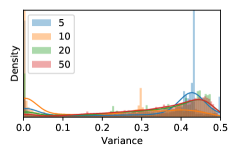

To model how different classifiers will respond to a given input , we assume that the prediction from classifier is sampled from a beta distribution that is characterized by two parameters by and . We further assume that is fixed to the same constant value for all ’s. Under this assumption, each input can be described by ( can be calculated since is fixed), easing further analysis. The Severity Level (SL) of the case represented by image can be characterized by the parameter . The larger the value of , the more severe the case of is. When and are close, the case is ambiguous as the distribution shifts towards being symmetric (i.e. signifying much disagreement among classifiers) rather than being one-sided (i.e. consensus among classifiers that is negative or positive). We provide a set of examples in Figure 2 and also Figure S.8 in the supplementary materials showing how the beta distribution can be used to capture diverse predictions given by an ensemble learner.

In contrast, the MC-dropout method showed the worst overall performance among the three, as it can be seen from the high ratios of SL0 examples among the uncertain negatives in Figure 4. The histograms in Figure 2 provides another perspective to look into the phenomenon, where a decent proportion of MC-dropout model’s predictions on SL0 inputs entailed low confidence (far from 0 or 1), which from another angle explained why MC-dropout was less specific in terms of lower FNP; many no-DR inputs (i.e. SL0) were erroneously assigned high uncertainty by MC-dropout models.